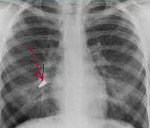

T17.8 Инородное тело в другом или нескольких отделах дыхательных путей